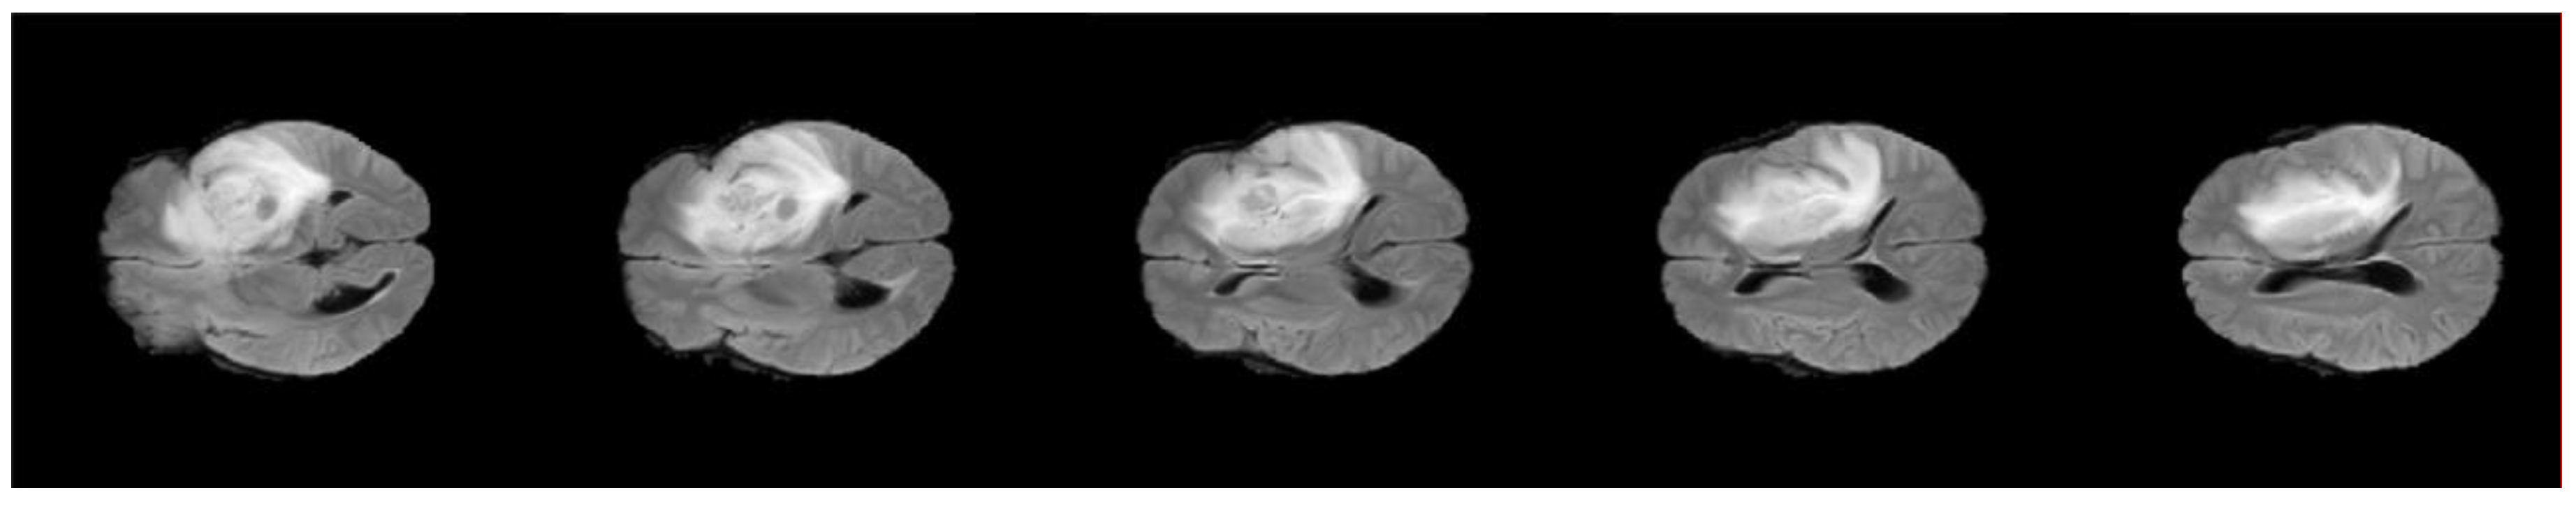

Segmentation of MRI brain tumor scans always challenged by poor image quality, the main cause for image degradation in MRI is the contamination of the MRI images with noises like irregularities [37]. Pre-processing operations are required to enhance the image quality, the target for these procedures is to reduce the contaminated noise and improve segmentation of image edges by eliminating inhomogeneous areas of the image. In the proposed model, four steps were applied: conversion of the 3D-MRI into 2D slices, skull-stripping, anisotropic diffusion, and contrast enhancement. Figure 5 shows an example of one patient’s 2D slices after pre-processing. Herein, the conversion process was applied using 3D Slicer, which is an open- source software web application for medical image informatics, image processing, and three-dimensional visualization.

Figure 5.

Example of one volume after pre-processing.

Skull-stripping comprises three steps involving morphological operations: Step 1: The input 2D-MRI slices are converted to binary images using Otsu’s thresholding. Step 2: Dilation and erosion operations are undertaken to preserve the minute features of the brain in the resultant 2D-MRI slices (creation of the mask). By filling the holes, the brain becomes a complete connected component. Step 3: (Superimposition): The final skull stripped image is obtained by superimposing the mask on the input image [37]. An anisotropic diffusion filter is employed to diminish the noise in the image and homogenize it in regions having a similar grey level by preserving regions’ edges. As a generalization of the diffusion process, anisotropic diffusion filter creates a set of parameterized images, such that each image in the resulting images is a fusion of the original image and an original image local content-based filter. Therefore, anisotropic diffusion is a space variant and non-linear transformation of the original image. See reference [38] for more information. Finally, contrast enhancement is applied using a histogram equalization technique in which the tumor conspicuity is improved by redistributing the greyscale of the images in a non-linear way to advance the separation of latent or hidden variations in pixel intensity into a more visually discernible distribution, thus taking advantage of the human vision physiological attributes [37,38].